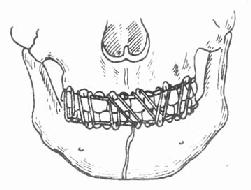

3.骨间结扎固定:手术切开复位的病例,可在骨折两断端钻孔,然后穿过不锈钢丝作结扎固定(图4-20)。这也是一种可靠的固定方法。小儿颌骨骨折和无牙颌骨骨折,也可用此法固定。

图4-20 骨间结扎固定法